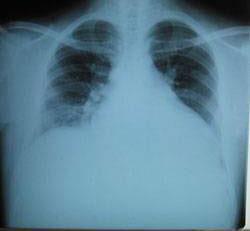

擴張性心肌病是一種嚴(yán)重的心臟疾病,但“心之港灣”為你帶來希望,這里的專家團隊一直在深入研究擴張性心肌病的最新治療方法,并深知每位患者都渴望得到最佳的治療和關(guān)懷,他們努力不懈,為患者帶來生機和新生。